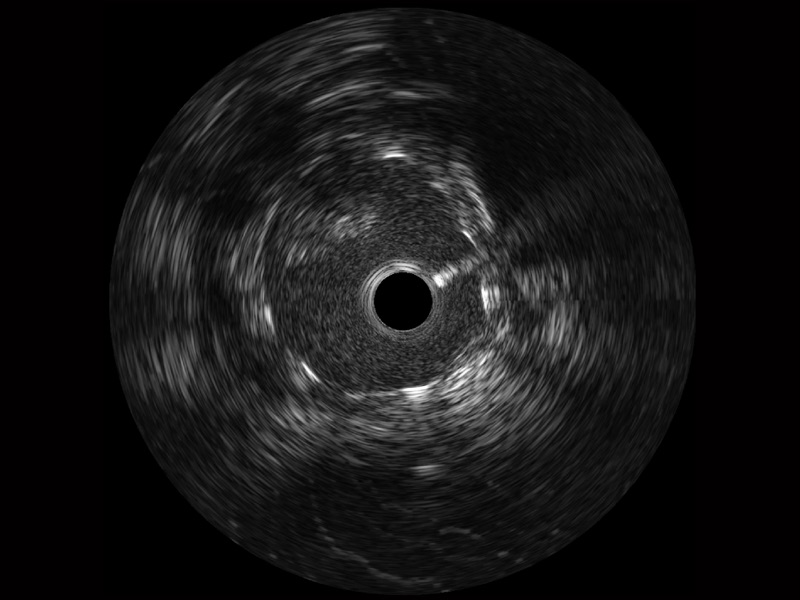

云顶集团官网宽频IVUS图像

对比传统IVUS导管成像,云顶集团官网宽频IVUS图像的近场支架梁显影更细腻,远场中膜外血管仍清晰可辨,兼顾远中近,兼顾分辨力与穿透深度